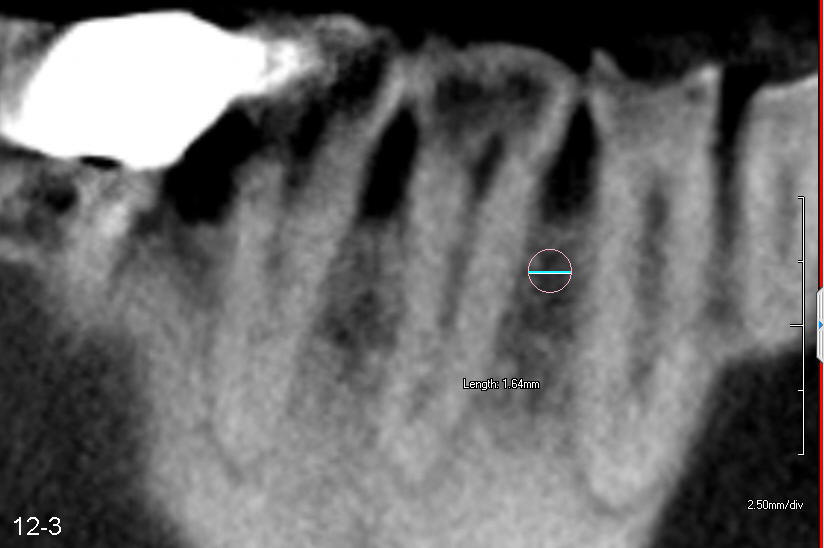

Fig.12-3 (CBCT: sagittal section): A mini-implant (1.6 mm in diameter) will be placed between the teeth #27 and 28.